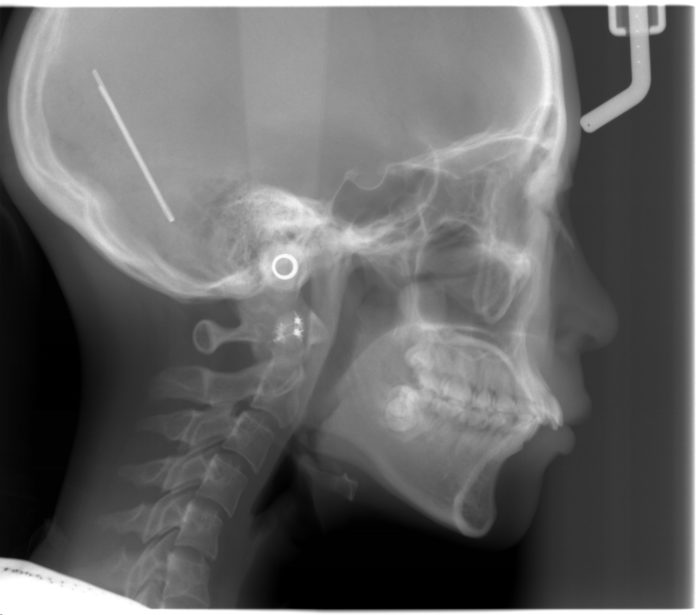

出っ歯(上顎前突)になりやすい理由

指をくわえると、上の前歯や上あごに常に前方向の力が加わります。その結果、前歯が徐々に前に傾き、口元が出て見える「出っ歯」になってしまうことがあります。

開咬(かいこう)のリスク

長期間指しゃぶりやおしゃぶりをしていると、前歯が上下で噛み合わずにすき間ができる「開咬」になることもあります。これにより、

骨の大きさや位置など骨格に由来する出っ歯は2つのタイプに分けることができます。

①上顎が大きすぎるため顎ごと前に出ているタイプ

②下顎が小さく上顎に対して下顎が奥に入りすぎているタイプ